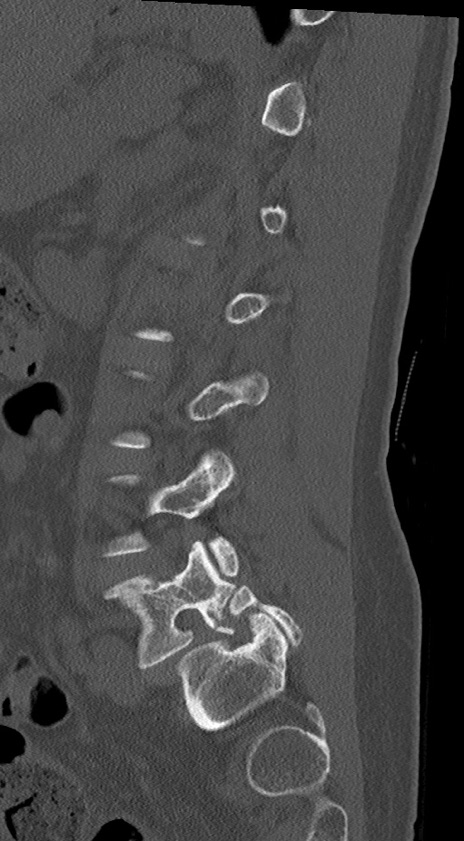

腰椎CT

冠状断像